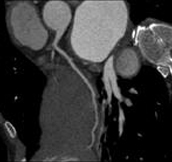

0,5 sec/rotation, BP (BeamPitch) 1.08, 0.625mm slice width, 500mA (250mAs). High-pitch scanning possible for routine examination. 475 mm abdomen scannable within 5.5 seconds.

0.5 sec/rotation, BP 1.08, 0.625mm slice width, 360mA (180mAs).High-pitch scanning is possible for routine examination400 mm chest can be scanned within 4.7 seconds.